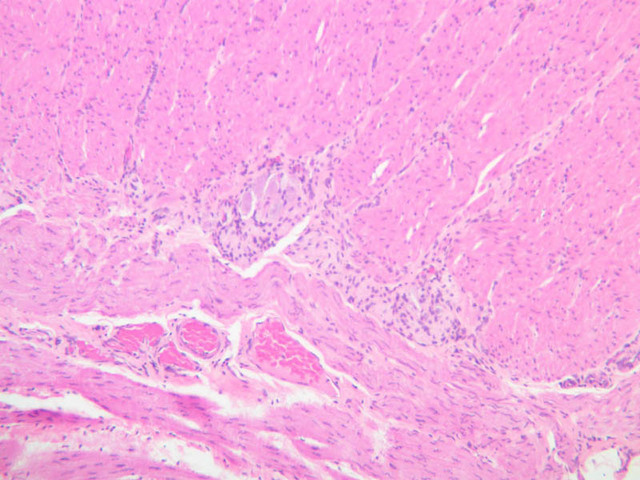

Examine the submucosal, external muscular and serosal layers in one of the sections of stomach. Note the numerous blood vessels in the submucosa and try to find elements of Meissner's submucosal plexus. Study the muscularis externa, noting that it is not always possible to distinguish an inner oblique layer, since this layer occurs only in the corpus and is never as prominent as either the circular or longitudinal layers. Look between the outer two external muscular layers for profiles of the neural elements of Auerbach's myenteric plexus. It is through the contractions of the muscularis externa that gastric secretions are mixed with ingested food to yield the semifluid chyme, which is passed on to the duodenum. Although the connective tissue and mesothelium of the gastric serosa are disrupted in some of your sections, you should be able to find intact regions of serosa. What is the function of this layer?